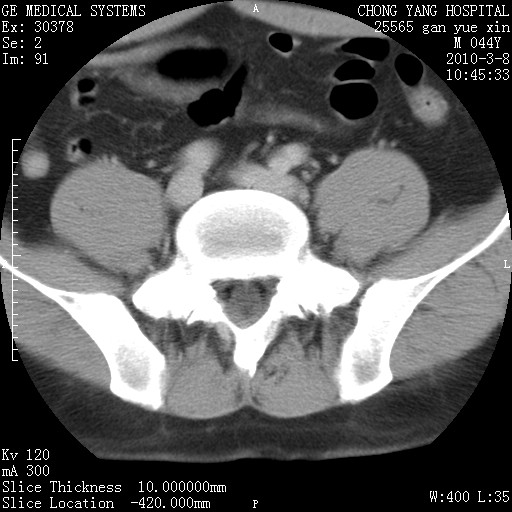

标题: CT24940:主动脉增强,典型病例。 [打印本页]

标题: CT24940:主动脉增强,典型病例。

夹层动脉瘤。

动脉夹层

夹层动脉瘤,典型

主动脉夹层。

动脉夹层的分型:

⒈debakey分型:根据主动脉夹层累及部位,分为三型:ⅰ型:原发破口位于升主动脉或主动脉弓部,夹层累及升主动脉、主动脉弓部、胸主动脉、腹主动脉大部或全部,少数可累及髂动脉。ⅱ型:原发破口位于升主动脉,夹层累及升主动脉,少数可累及部分主动脉弓。ⅲ型:原发破口位于左锁骨下动脉开口远端,根据夹层累及范围又分为ⅲa,ⅲb。ⅲa型:夹层累及胸主动脉。ⅲb型:夹层累及升主动脉、腹主动脉大部或全部。少数可累及髂动脉。

⒉stanford分型:a型:夹层累及升主动脉,无论远端范围如何。b型:夹层累及左锁骨下动脉开口以远的降主动脉。

夹层动脉瘤,少量胸水

夹层动脉瘤;左侧少量胸腔积液。

典型主动脉夹层。